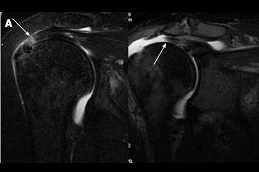

Results:

prp-injection-for-rotator-cuff-tear Clinic in Dubai Best prp-injection-for-rotator-cuff-tear Clinic in Dubai Best prp-injection-for-rotator-cuff-tear in Abu Dhabi